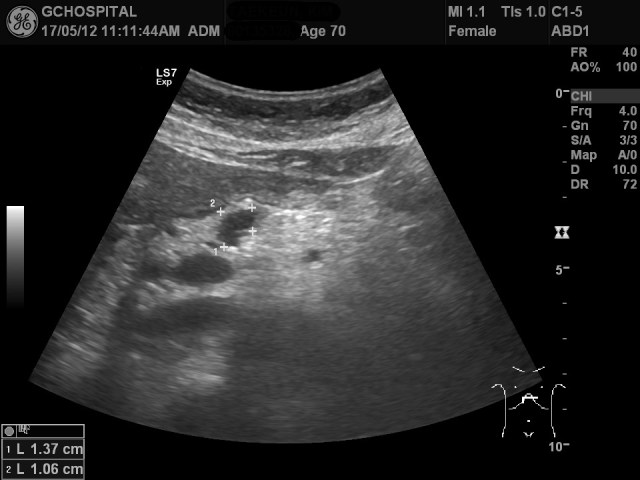

올해에도 췌장낭종의 추적관찰을 위해 내원하셔서 췌장부위를 촬영한 게 위의 영상입니다. 그런데, 영상에서 췌장낭종이 확인되지 않고 있습니다.

뿐만 아니라 췌장의 꼬리부위에 흐릿하게 저에코음영이 있는것처럼 보이기도 합니다. 과연, 췌장에 저에코의 종괴나 췌장염과 같은 병변을 의심해야 하는걸까요?

위 영상은 같은 시간이 지난 후에 다시 부른 후 환자의 자세를 semi-upright position으로 하고, 호홉을 조절하면서 다시 촬영한 영상입니다. 예전부터 보였던 췌장낭종을 선명하게 확인할 수 있습니다. 예전과 모양과 크기에 별다른 변화는 없었습니다.

췌장의 꼬리부위에서 의심스러웠던 저에코음영도 이번에는 전혀 보이지 않았으며, 전체적으로 균일한 에코음영의 췌장실질을 확인할 수 있었습니다.